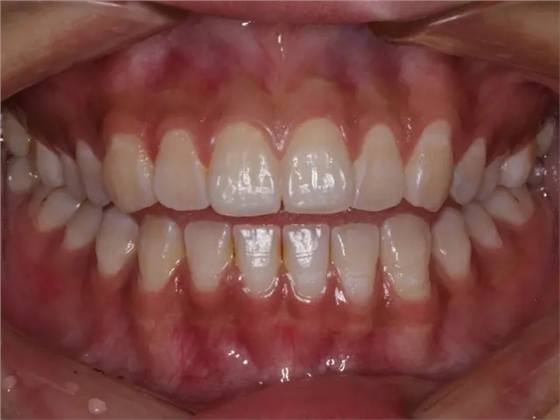

然后,第二磨牙造成咬合干擾、早接觸,前牙開 牙合…………